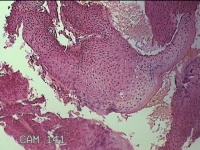

外阴赘生物

性别

女

年龄

33岁

临床诊断

外阴尖锐湿疣

一般病史

发现外阴尖锐湿疣4个月。

标本名称

大体所见

灰白暗红色不规则碎组织0.3x0.2x0.1cm一堆。

图4

良性病变,考虑湿疣。